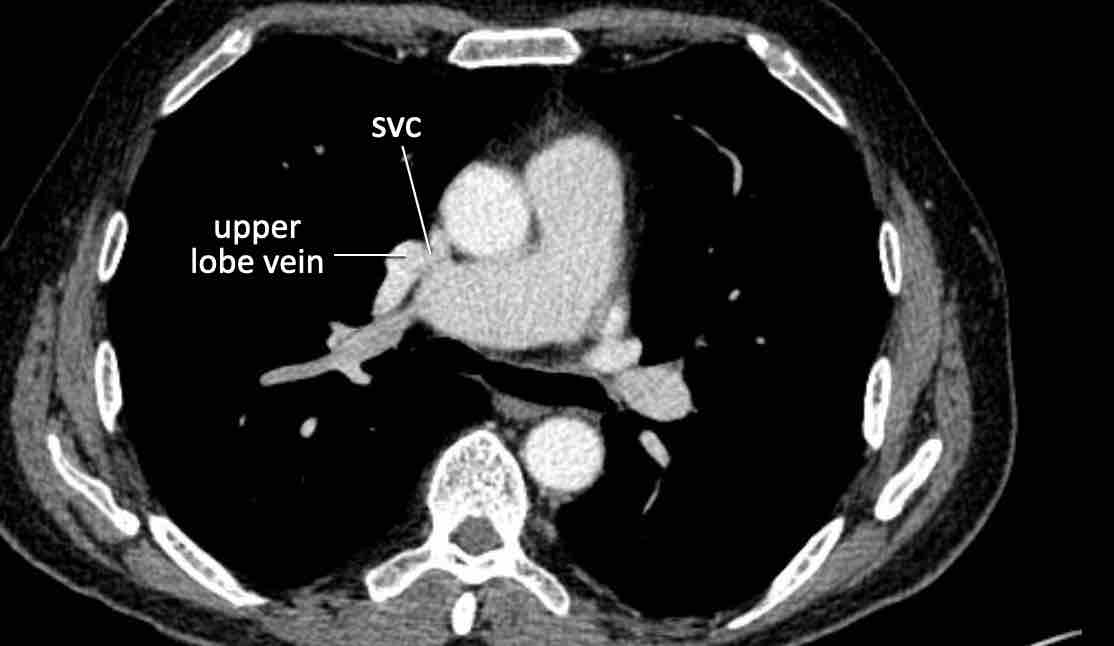

Trong PAPVR, thùy trên trái thường dẫn lưu vào tĩnh mạch tay đầu trái. Bất thường phổ biến tiếp theo là thùy trên phải dẫn lưu vào tĩnh mạch chủ trên.

PAPVR bên phải có mối liên quan chặt chẽ với thông liên nhĩ thể xoang tĩnh mạch (khoảng 40%), đây là một dạng thông liên nhĩ tại vị trí tiếp nối cavo-nhĩ. Do đó, cần kiểm tra sự hiện diện của dạng thông liên nhĩ này khi phát hiện PAPVR bên phải.

Hình ảnh

Bệnh nhân này được lên kế hoạch cắt thùy trên phải do ung thư phổi và bất thường mạch máu này ban đầu đã bị bỏ sót trên hình ảnh CT.

Những hệ quả trong phẫu thuật của bất thường như vậy nhấn mạnh tầm quan trọng của việc không bỏ sót các biến thể này.